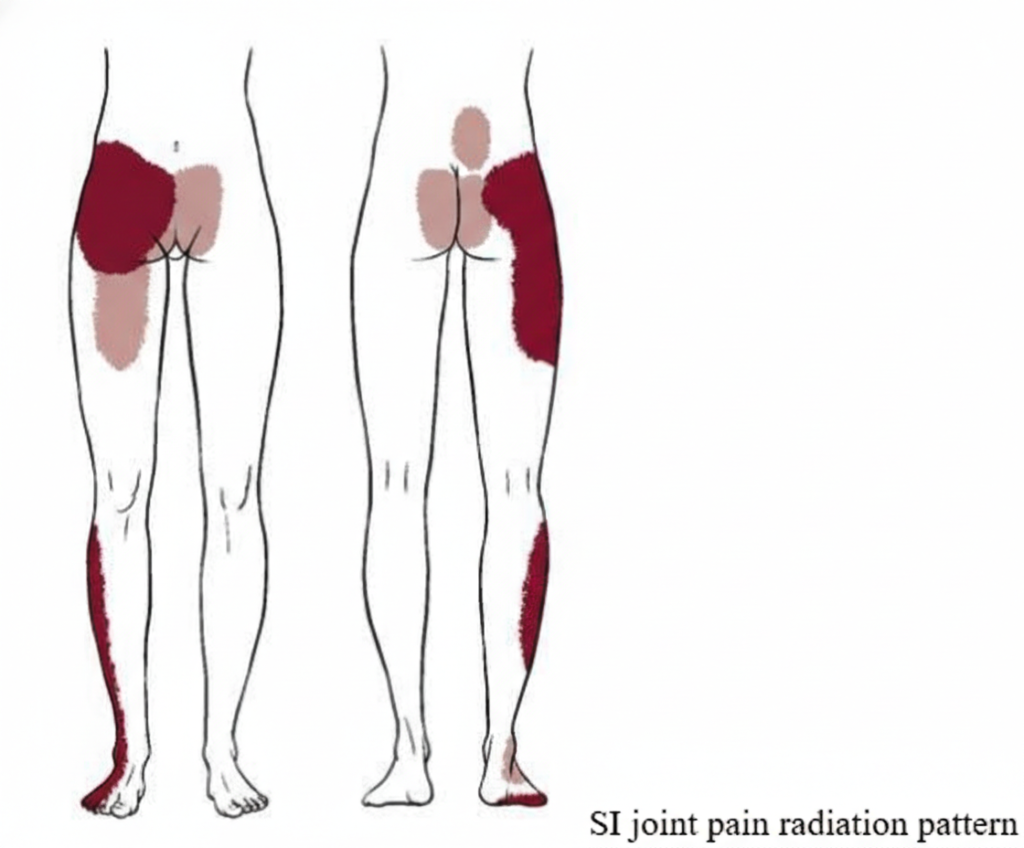

Sacroiliac (SI) Joint Dysfunction / Arthritis

What is the SI joint?

The sacroiliac joint connects the spine to the pelvis and is a major load-transferring joint.

Why it causes right-sided pain

SI joint dysfunction is often one-sided, especially on the right.

Key symptoms

- Pain just below the waistline on the right

- Pain radiating to buttock, groin, or thigh

- Worse with standing, walking, climbing stairs, or turning in bed

- Pain while getting up from sitting

Common causes

- Pregnancy

- Trauma or fall

- Leg length difference

- Degenerative arthritis

Frequently misdiagnosed as disc pain or sciatica